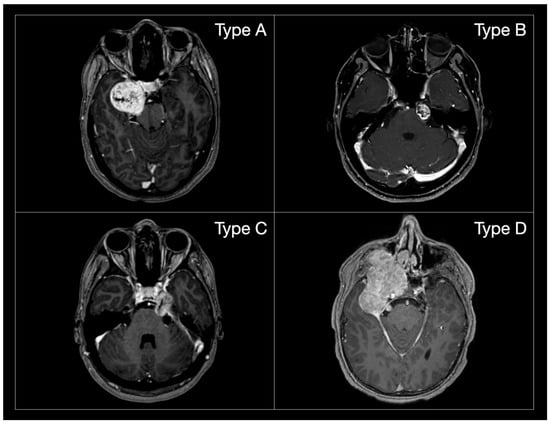

| Author | Year | Type of Studies | Cases | Surgeries | Mean age | ETOA % | EEA % | M-AL Apr. % | RSA % | Comb./2sps % | TMA % | A | B | C | D | Pre Trig. Imp. | Post Trig. Imp. | CSF Leak | Other Compl. | Recurrence | GTR | NTR | STR |

| Author | Samii Type | Number of Patients | ETOA | EEA | M-AL Approaches | RSA | Comb./2-steps | TMA |

|---|---|---|---|---|---|---|---|---|

| Aftahy et al., 2021 [4] | A | 6 | 0 | 1 | 5 | 0 | 0 | 0 |

| Chen et al., 2014 [14] | A | 13 | 0 | 0 | 13 | 0 | 0 | 0 |

| Choucha et al., 2024 [15] | A | 6 | 0 | 2 | 4 | 0 | 0 | 0 |

| Fukaya et al., 2010 [3] | A | 8 | 0 | 0 | 8 | 0 | 0 | 0 |

| Goel et al., 2010 [16] | A | 0 | 0 | 0 | 0 | 0 | 0 | 0 |

| Kong et al., 2023 [17] | A | 17 | 17 | 0 | 0 | 0 | 0 | 0 |

| Li et al., 2020 [18] | A | 8 | 0 | 0 | 8 | 0 | 0 | 0 |

| McCormick et al., 1988 [19] | A | 8 | 0 | 0 | 6 | 0 | 2 | 0 |

| Park et al., 2019 [6] | A | 9 | 5 | 4 | 0 | 0 | 0 | 0 |

| Patel et al., 2022 [23] | A | 6 | 0 | 6 | 0 | 0 | 0 | 0 |

| Samii et al., 1995 [11] | A | 5 | 0 | 0 | 5 | 0 | 0 | 0 |